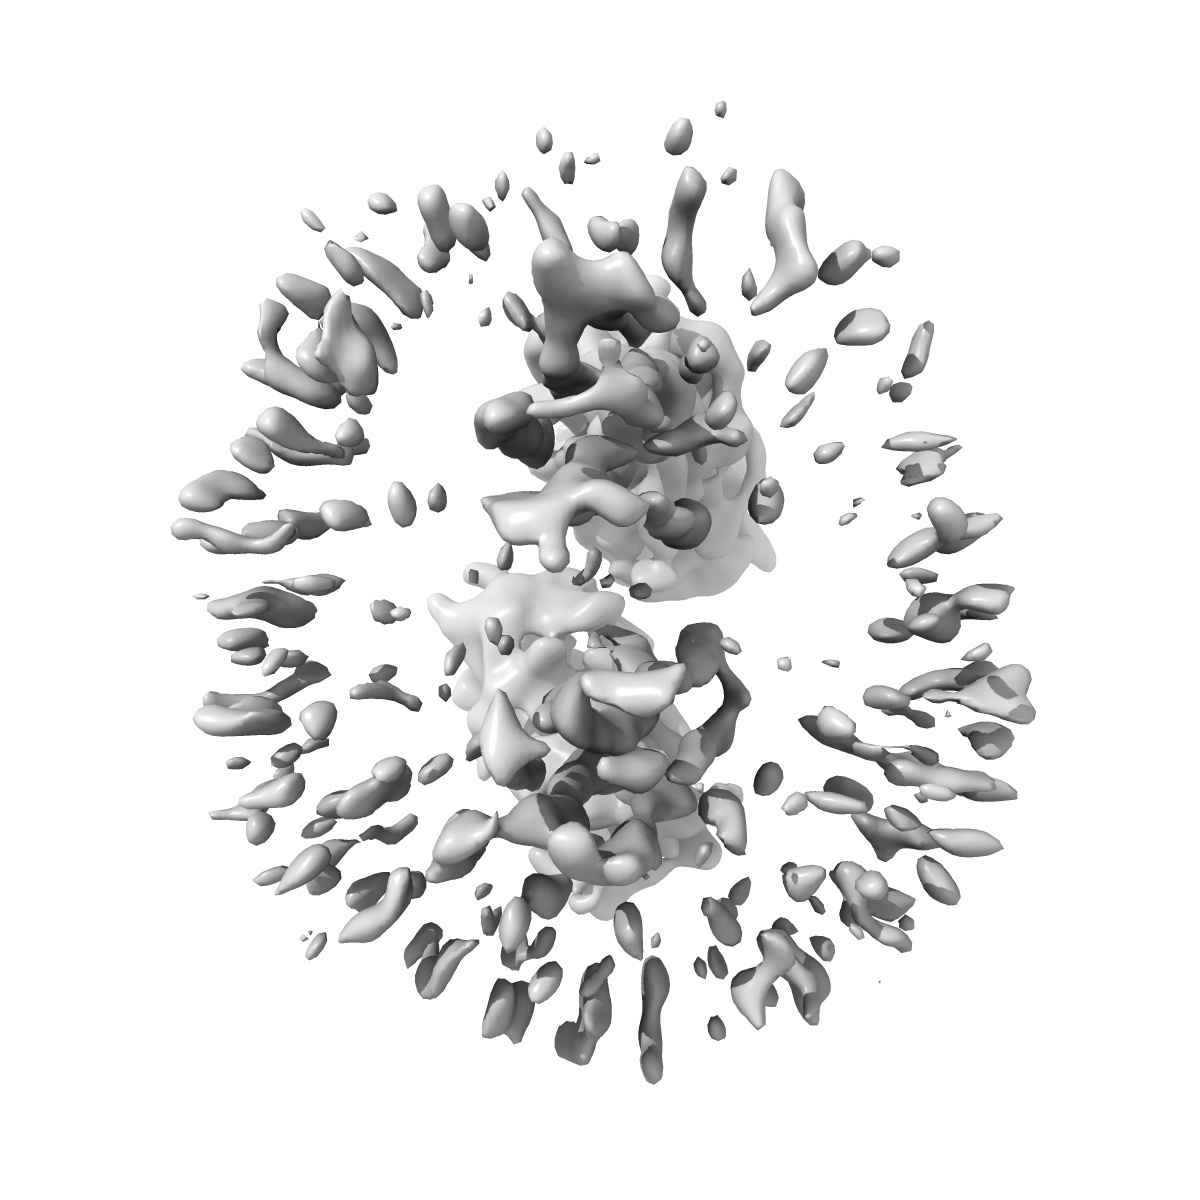

Cryo-EM structure of mGlu2-mGlu4 heterodimer bound mGlu4 agonist E7P

Sample: mGlu2-mGlu4 heterodimer bound L-AP4

Structural basis of orientated asymmetry in a mGlu heterodimer.

Huang W, Jin N, Guo J, Shen C, Xu C , Xi K , Bonhomme L, Quast RB , Shen DD, Qin J, Liu YR , Song Y, Gao Y , Margeat E , Rondard P , Pin JP , Zhang Y , Liu J

(2024) Nat Commun , 15 , 10345 - 10345